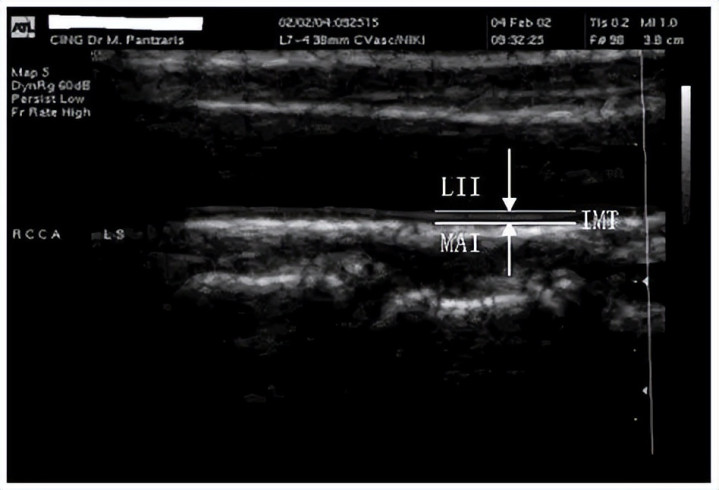

颈动脉内膜中层厚度(IMT)

咱们可以把血管想象成一根水管,IMT就是水管壁的“厚度”。如果水管壁增厚,说明里面开始积“水垢”,医学上叫动脉粥样硬化。目前临床上最常用的是颈动脉B超测IMT值。

正常成年人,颈动脉IMT一般小于0.9mm;IMT超过1.0mm,就是“早期动脉硬化”的提示,预警值;超过1.2mm,甚至发现“斑块”,就是危险级别。

IMT测量过程无创、快捷,只要做一个颈部B超就能看到结果。越来越多医院会把这个数据写进体检表,建议40岁以上人群每年都要查一次。